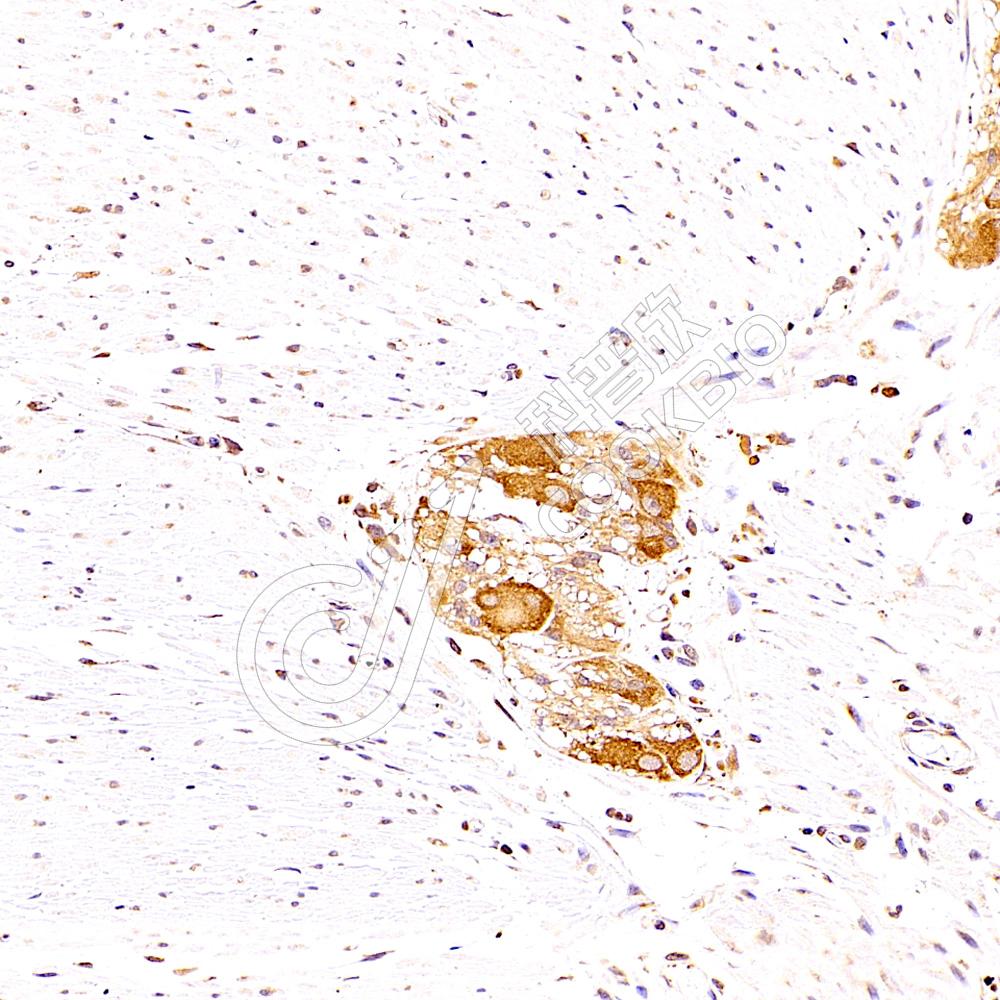

IHC检测SUV3L1蛋白(货号 K1338334).

样品: 人神经节, 4%多聚甲醛 (货号KSG1101) 固定12-24小时.

抗原修复: 柠檬酸抗原修复液(干粉, pH 6.0) (KSG1201), 98℃, 20分钟.

—抗: 1: 1100稀释, 4℃ 孵育过夜.

二抗: S-vision免疫组化多聚二抗(山羊抗兔),即用型 (货号KB3906), 室温孵育20分钟.